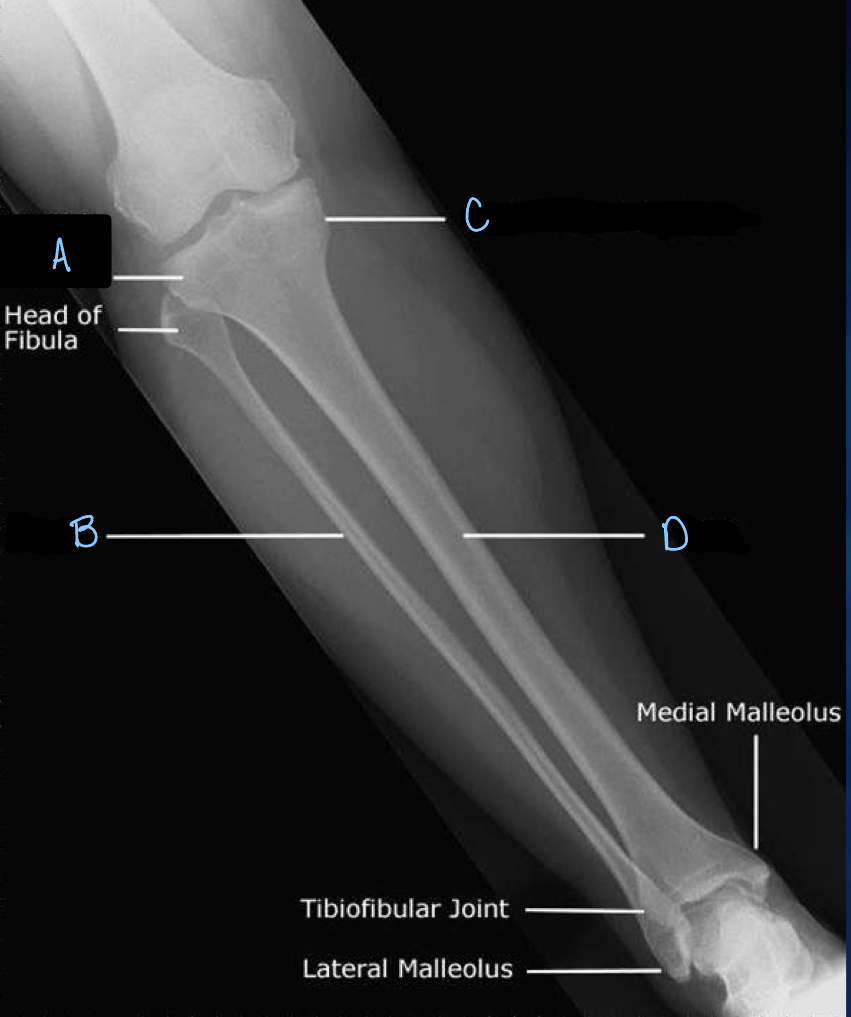

1

What is A?

lateral tibial condyle

2

What is B?

fibula

3

What is C?

medial tibial condyle

4

What is D?

tibia

5

patella

6

7